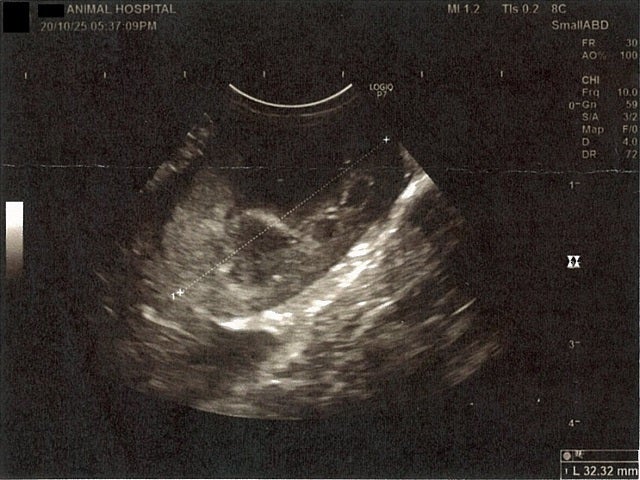

《心臓周りの胸部以外の全ての腹部で腹水がみられるとの診断です》

大網という部分で内臓を包む膜のようなものです。その周りに腹水が溜まっています。

右腎臓周りに腹水が確認できるエコー写真